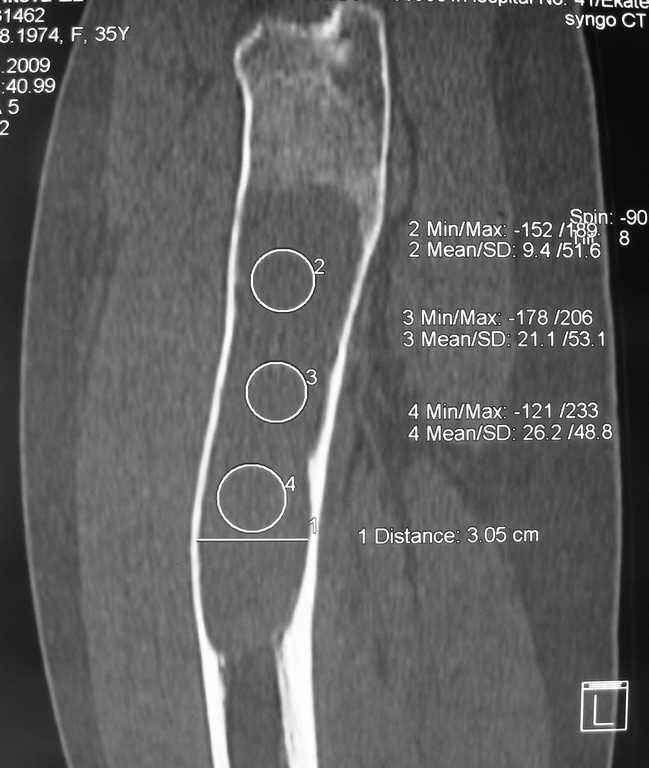

Re: Фиброзная дисплазия-продолжение